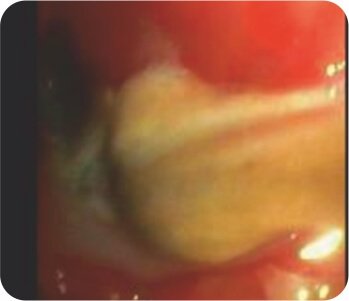

ব্রঙ্কোস্কোপি - বাম উপরের লোব ব্রঙ্কাসে ভর/জমাট বাঁধা

আক্রমণাত্মক মিউকার মাইকোসিস (ব্রড অ্যাসেপ্টেট হাইফা) এর প্রসারিত ভরের ক্রিবায়োপসি